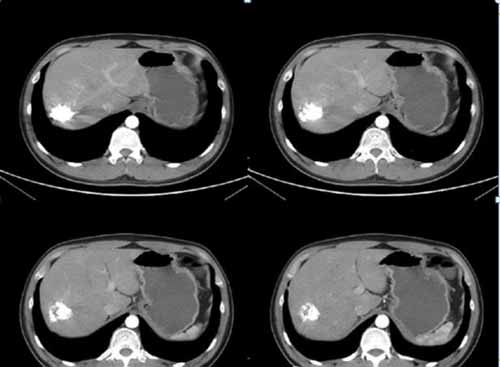

我們來看一個典型病例:

(術后復查肝血管瘤固縮,栓塞劑沉積良好,無復發)